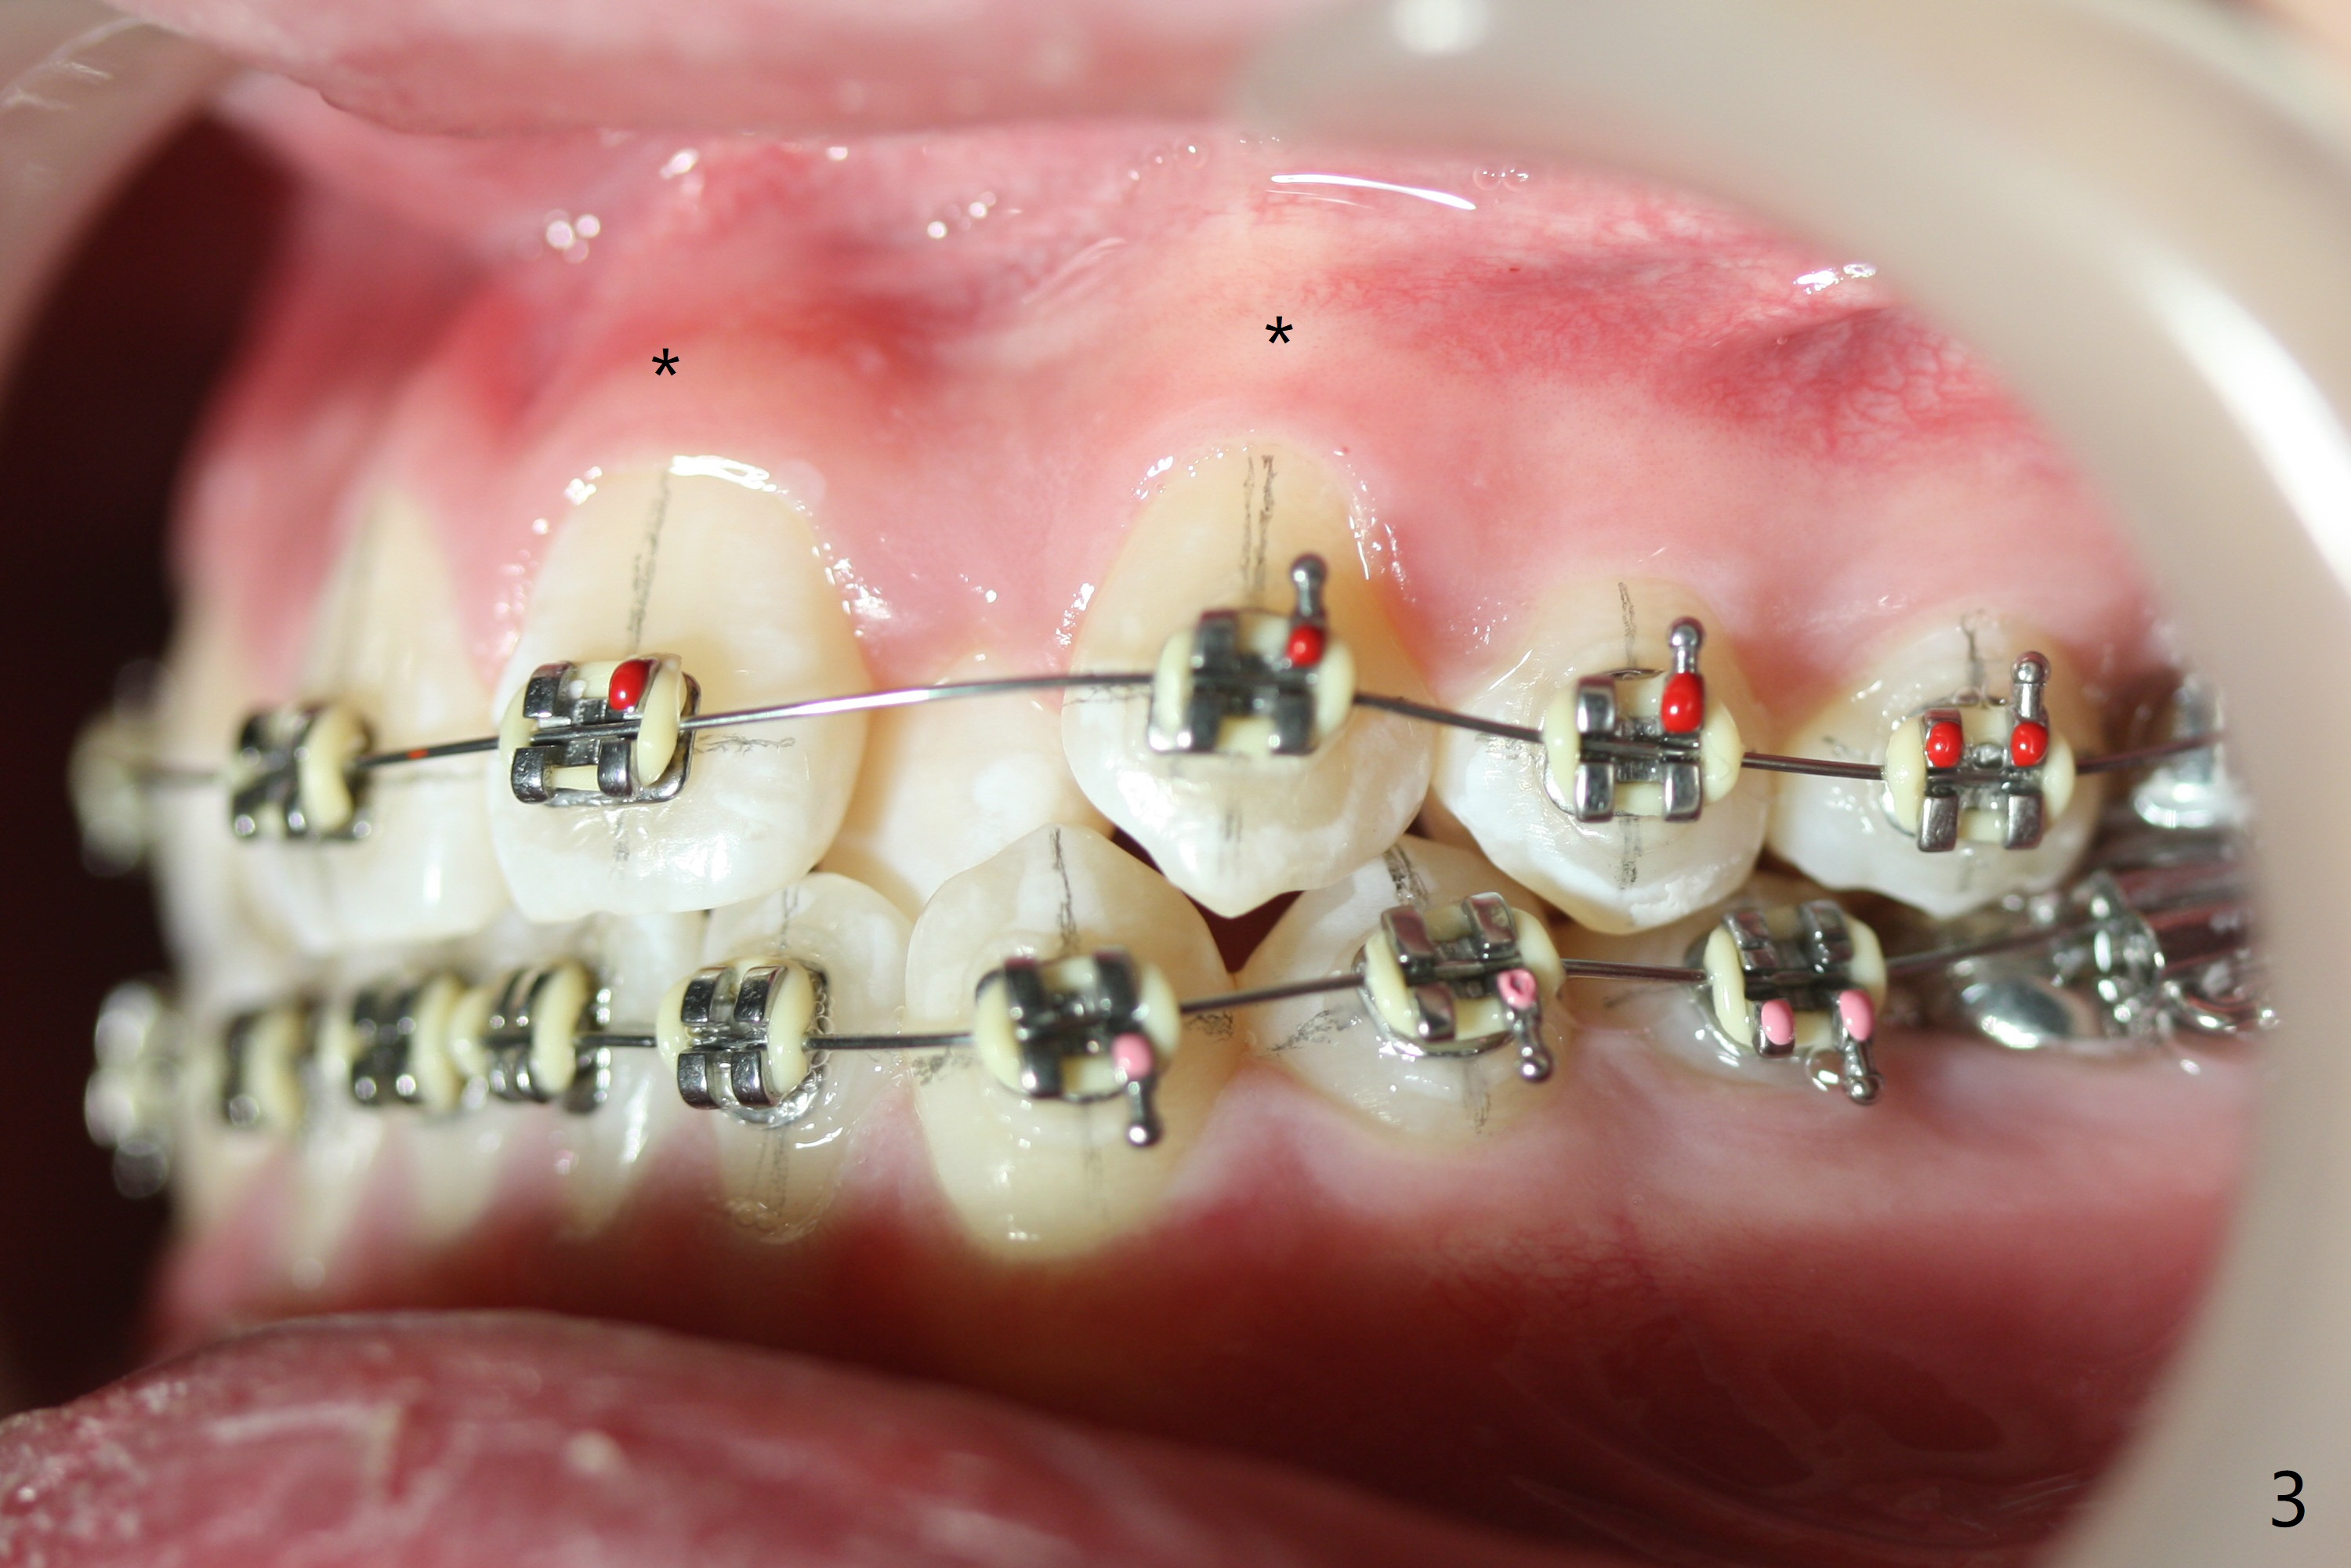

Cephalometric analysis shows Class III skeletal relationship. The roots of the upper anterior teeth (Fig.1,3 *) are prominent before treatment. In order to correct the cross bite of U2s (Fig.2,5), the upper arch needs expansion (Fig.4). Will the arch expansion cause buccal plate loss of the upper teeth? The upper dental midline matches the lower one by using the left open coil spring only (4 months 10 days post banding, Fig.6).